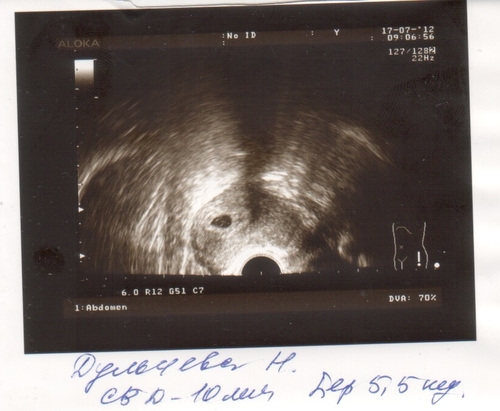

УЗИ двухплодной беременности на 5 неделе: Подборка изображений

Раздел: Калейдоскоп образов